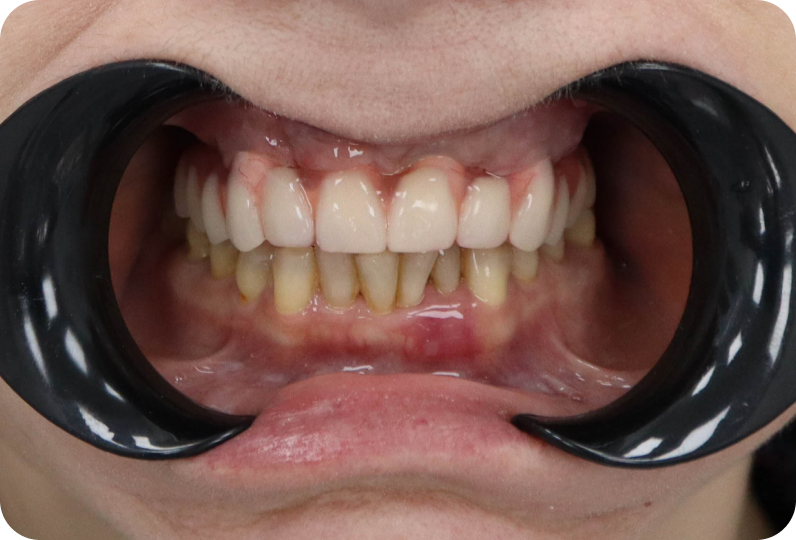

результаты

Установлен условно-съемый металлоакриловый протез на 12 зубов

ALT

Вид протеза сбоку